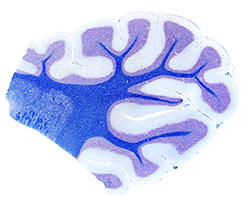

Órganos Nerviosos II

Órganos Nerviosos II

Cerebelo y corteza cerebral.

(10 preparaciones) -